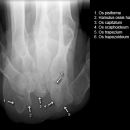

Os pisiforme

Zusatzaufnahme bei V.a. Verletzung des Os pisiforme. Grundsätzlich gilt jedoch die großzügige CT-Indikation bei unklaren Befunden!!!

Beurteilungskriterien

• Nur Os pisiforme beurteilen! Fraktur?

• Regelrechte Artikulation mit dem Triquetum?

• Akzessorische Knöchelchen (abgerundete, zirkulkär-geschlossene Kortikalis)

• Weitere abgrenzbare erkennbare Strukturen: Lunatum, Trapezium

Carpal-Tunnel

U-förmige Darstellung des Karpaltunnels mit überlagerungsfreier Projektion des Os pisiforme, des Hamulus ossis hamati und des Daumensattelgelenks – jedoch CT überlegene Alternative!

• scharfe Abgrenzbarkeit von Pisiforme, Hamulus ossis hamati und Daumensattelgelenk

• volare Konturen von Capitatum, Scaphoid und Triquetum

• akzessorische Knöchelchen, Fremdkörper, Kalkeinlagerungen in Projektion auf den Karpaltunnel? Weichteilschwellung?

• Kalkanlagerungen in Projektion auf den Carpaltunnel -> CT?